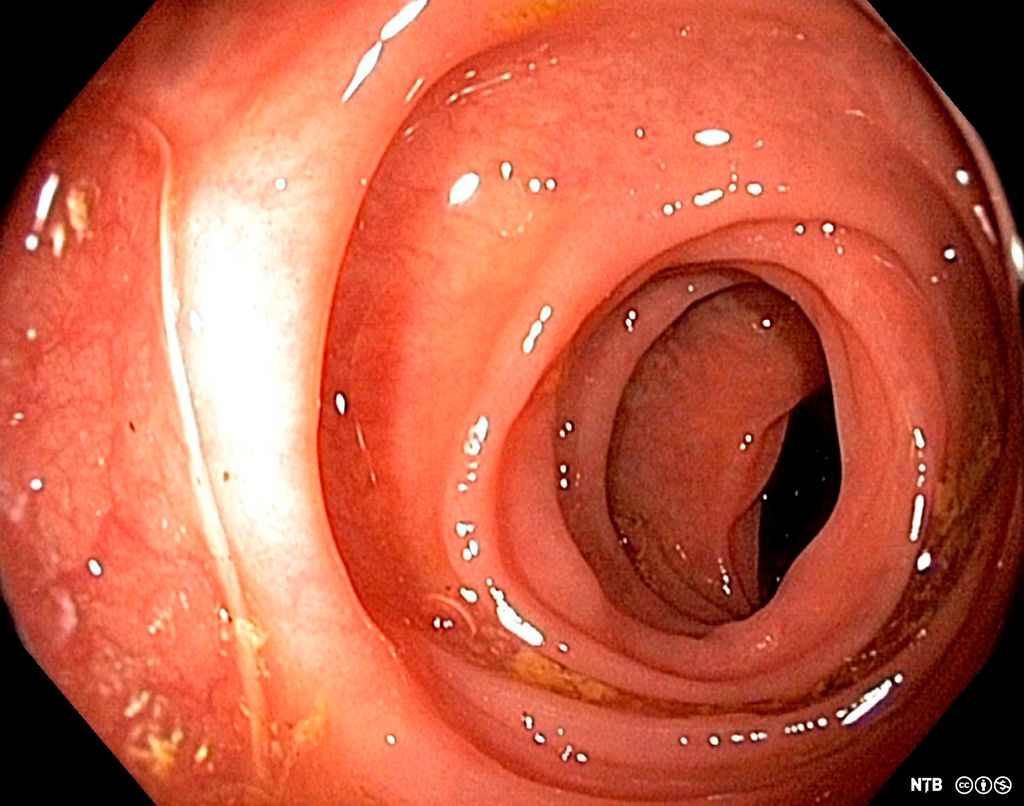

Slimhinner er vev som dekker overflaten av luftveiene, fordøyelsessystemet og alle andre kroppsåpninger og indre hulrom som er i kontakt med omverdenen. Selve slimet som skilles ut på slimhinnene, utgjør en viktig fysisk barriere. Tarmen inneholder trillioner av bakterier som kan gjøre stor skade dersom de kommer seg gjennom slimhinnene.